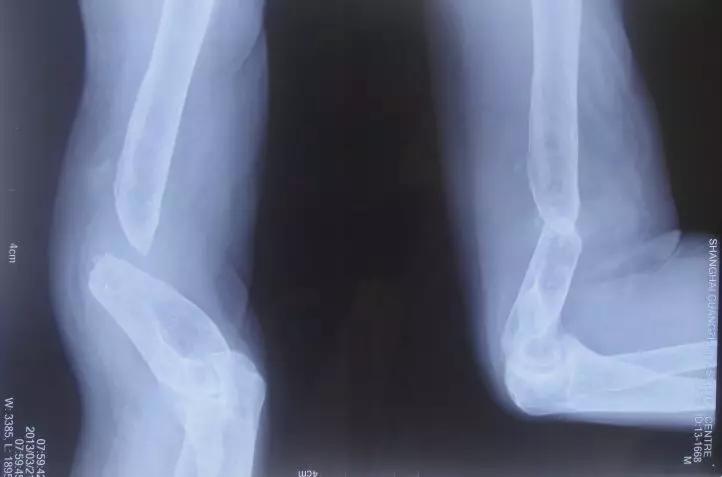

骨不连的诊断和治疗方法上海六院陈华科普系列

患者男,49岁,因胫腓骨开放性骨折行外固定支架固定,腓骨钢板螺钉固定